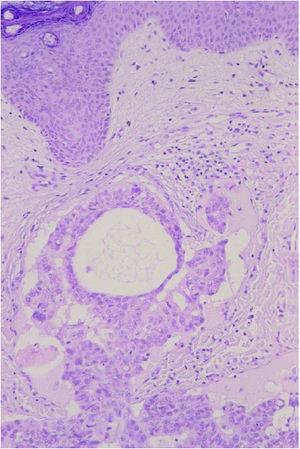

Un varón de 62 años, sin antecedentes personales de interés, ingresó en el hospital para estudio de una anemia microcítica de 4 meses de evolución y diarrea. Desde hacía 2 meses el paciente presentaba unas lesiones cutáneas eritematosas, asintomáticas, localizadas en la fosa iliaca, ingle y tercio superior del muslo izquierdo, previamente diagnosticadas como herpes zóster por su médico de familia y tratadas con famciclovir oral sin mejoría. En la exploración física se observaban múltiples pápulas y vesículas sobre una base eritematosa, infiltradas, localizadas en la fosa iliaca, pubis, ingle, y tercio superior del muslo izquierdo, distribuidas siguiendo el dermatoma L1-L2 (fig. 1). Se acompañaban de un discreto linfedema del miembro inferior izquierdo. Se practicó biopsia cutánea cuyo estudio histopatológico mostró una epidermis normal, sin evidencia de infección viral y una dermis cuyos vasos linfáticos aparecían permeados por grupos de células de aspecto tumoral (fig. 2). Estas células eran grandes, pleomórficas, algunas de citoplasma claro con el núcleo desplazado hacia la periferia, remedando un «anillo de sello» (fig. 3). Estos hallazgos eran compatibles con una invasión linfática diseminada por células de un adenocarcinoma pobremente diferenciado. Ante estos datos y por la clínica que tenía el paciente se solicitó una colonoscopia, con la que se apreció una formación de características malignas en recto, tendente a estenosar. El estudio histopatológico de la lesión fue de adenocarcinoma de recto. Se completó estudio con gammagrafía ósea, en el que no se hallaron metástasis óseas y tomografía computarizada (TC) toracoabdominal en el que se observó, aparte de la masa tumoral, una adenopatía en área inguinal izquierda y adenopatías retroperitoneales altas de características metastásicas. El paciente fue intervenido quirúrgicamente y remitido al Servicio de Oncología para tratamiento con quimioterapia y radioterapia.

Fig. 3.--Células grandes, pleomórficas, algunas de citoplasma claro con el núcleo desplazado hacia la periferia remedando un «anillo de sello». (Hematoxilina-eosina, ×100.)